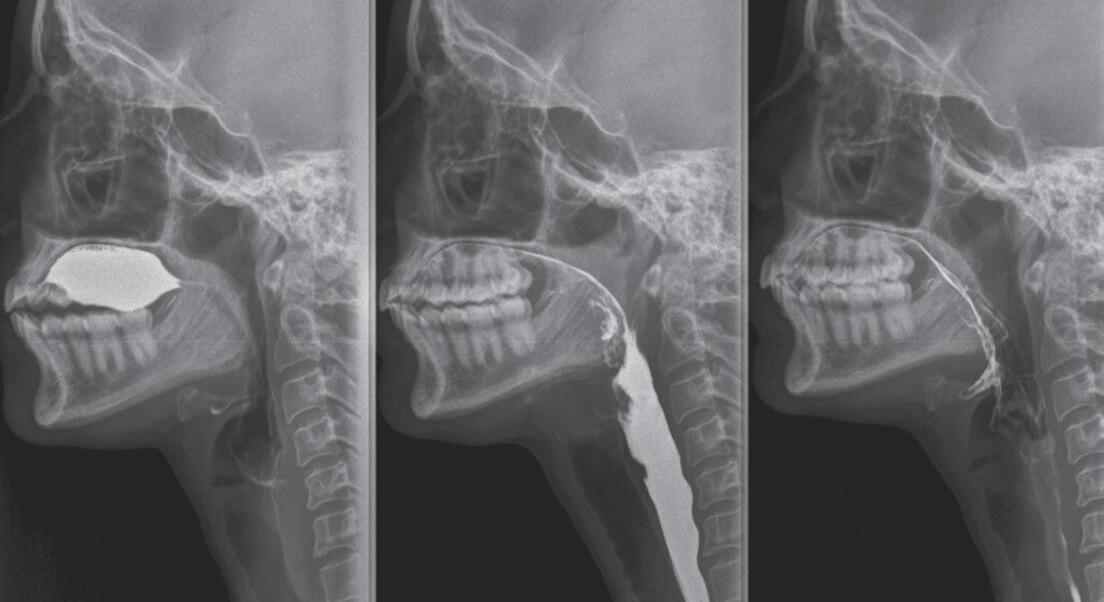

Fig. 1-3. Demonstração das fases da deglutição em visão lateral nas imagens de videofluoroscopia. (a) Fase preparatória oral: incisão dos dentes na bolacha com a raiz de língua elevada, véu palatino abaixado e via aérea aberta; (b) fase preparatória oral: bolo alimentar na porção central da língua com a raiz de língua elevada, véu palatino abaixado e via aérea aberta; (c) fase oral: ejeção do bolo para a região da orofaringe com o movimento anteroposterior de língua e via aérea aberta; (d) fase faríngea: fechamento do véu palatino, elevação da laringe e do osso hioide, PPF = parede posterior de faringe.

Fig. 1-5. (a, b) Demonstração do bolo alimentar em cavidade oral na imagem videofluoroscópica em visão anteroposterior.